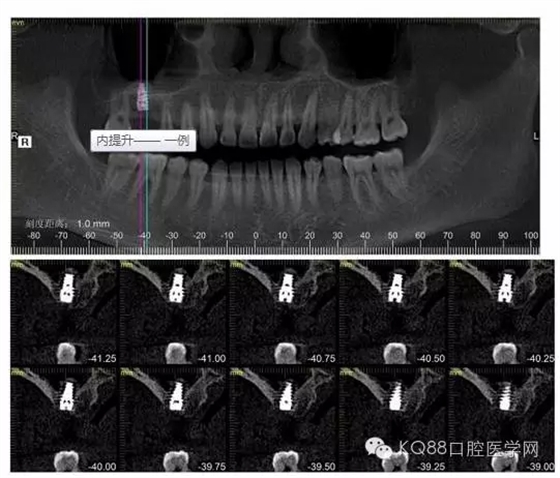

下面是拔牙前 CBCT

清晰可見(jiàn)根尖部陰影區(qū)域明顯。遠(yuǎn)中頰根

近中頰跟,同時(shí)可以看出離上頜竇比較近,且伴有骨缺損。

這個(gè)切面可以看到根裂。